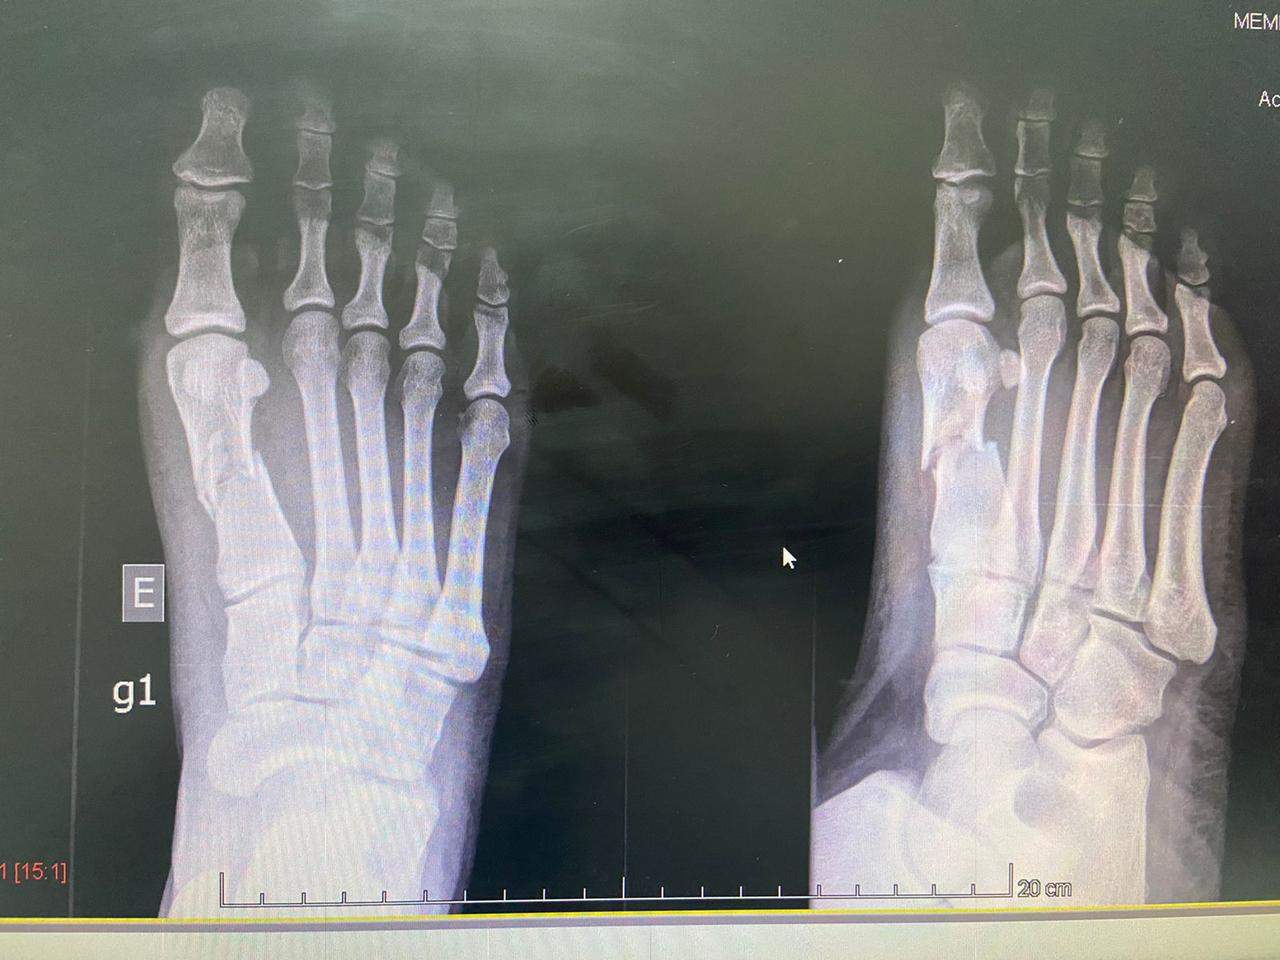

Uma mulher denunciou as agressões do namorado durante uma discussão. No relato, ela conta que teve o pé quebrado com golpes de capacete. O crime ocorreu no último fim de semana, na Grande Vitória, Espírito Santo.

"Ele estava com ciúmes porque eu ia sair com uma amiga minha e começou a ter um surto. Aí começou a discussão, as agressões. Quando eu tentei ir embora, ele me deu um 'mata-leão' , me botou dentro de casa novamente, e era soco, chute, e chegou ao ponto de quebrar meu pé com capacete”, relatou a jovem ao G1.

Ainda de acordo com a mulher, o suspeito machucava os pés dela para que as marcas não fossem características de agressões.